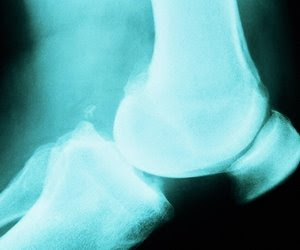

Günümüzde özellikle hareketsizliğin artması, yanlış beslenme, çevre kirliliğine ve buna bağlı toksin birikimleri ve fazla araç kullanımı sonucu kazalarda artış gibi pek çok nedene bağlı olarak, eklem ve kemik problemlerinde ciddi bir artış görülmektedir. Dolayısıyla, hareket sistemi ağrıları ve problemleri gittikçe artan bir sorun haline gelmiştir.